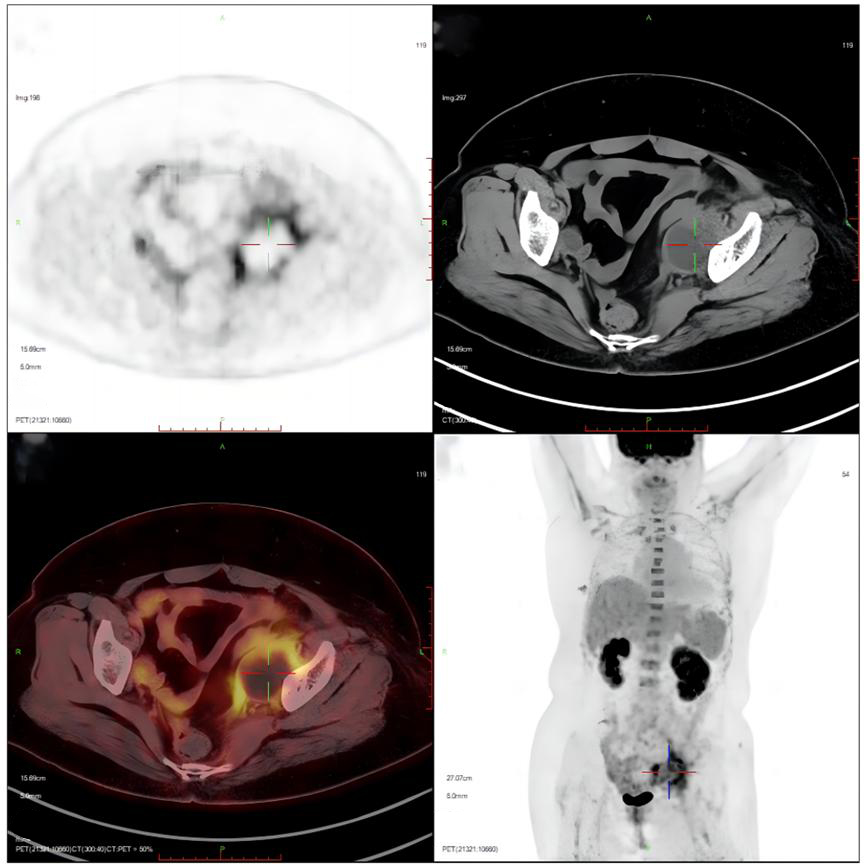

Ancillary investigations: Ultrasound + Doppler (lower extremity arteries): both lower extremity arteries were patent. Colour pelvic ultrasound: anechoic left iliac fossa, about 4.7 cm × 4.3 cm, with punctate echoes and poor translucency. PET-CT: left pelvic cystic foci, lymphocysts with infection (Figure 1). Blood count: haemoglobin 78 g/L. Blood culture: negative.

Figure 1

Figure 1. The result of positron emission tomography (PET-CT). Suggestive of left pelvic cystic foci surrounded by patches of irregular soft tissue with increased glucose metabolism, consider lymphocysts with infection.